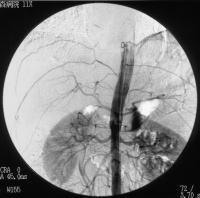

| 肝細胞癌(HCC)は、肝硬変やB型・C型肝炎ウイルス(HBV・HCV)感染などと 関連が多い肝細胞癌類似の細胞より構成される上皮性悪性腫瘍である。 画像診断法として、Dynamic CTでの早期(動脈相)で強い腫瘤のenhancement及び 後期(後期実質相・門脈相)での相対的な低吸収域化はHCCとして典型的といえる。 治療法としては、外科的手術の他にPEIT・PMCTなどの局所療法やTAE(科学塞栓療法) が行われている。 |

| 今回はTAEの一例を紹介する。TAEはAngio下で、腫瘍の栄養血管を ゼラチンスポンジなどの塞栓物質で、抗癌剤の投与と合わせて塞栓し 腫瘍を虚血状態にして壊死させようというものである。 通常、肝の流入血管は80%が門脈血、20%が肝動脈血であるのに対し HCCはほぼ100%の血流を肝動脈から得ているが肝動脈の分岐形式は 多様であって、この症例も希な例といえる。 |

この症例は、CT上S8領域にHCCを認めたが肝動脈造影、上腸間膜動脈造影では |